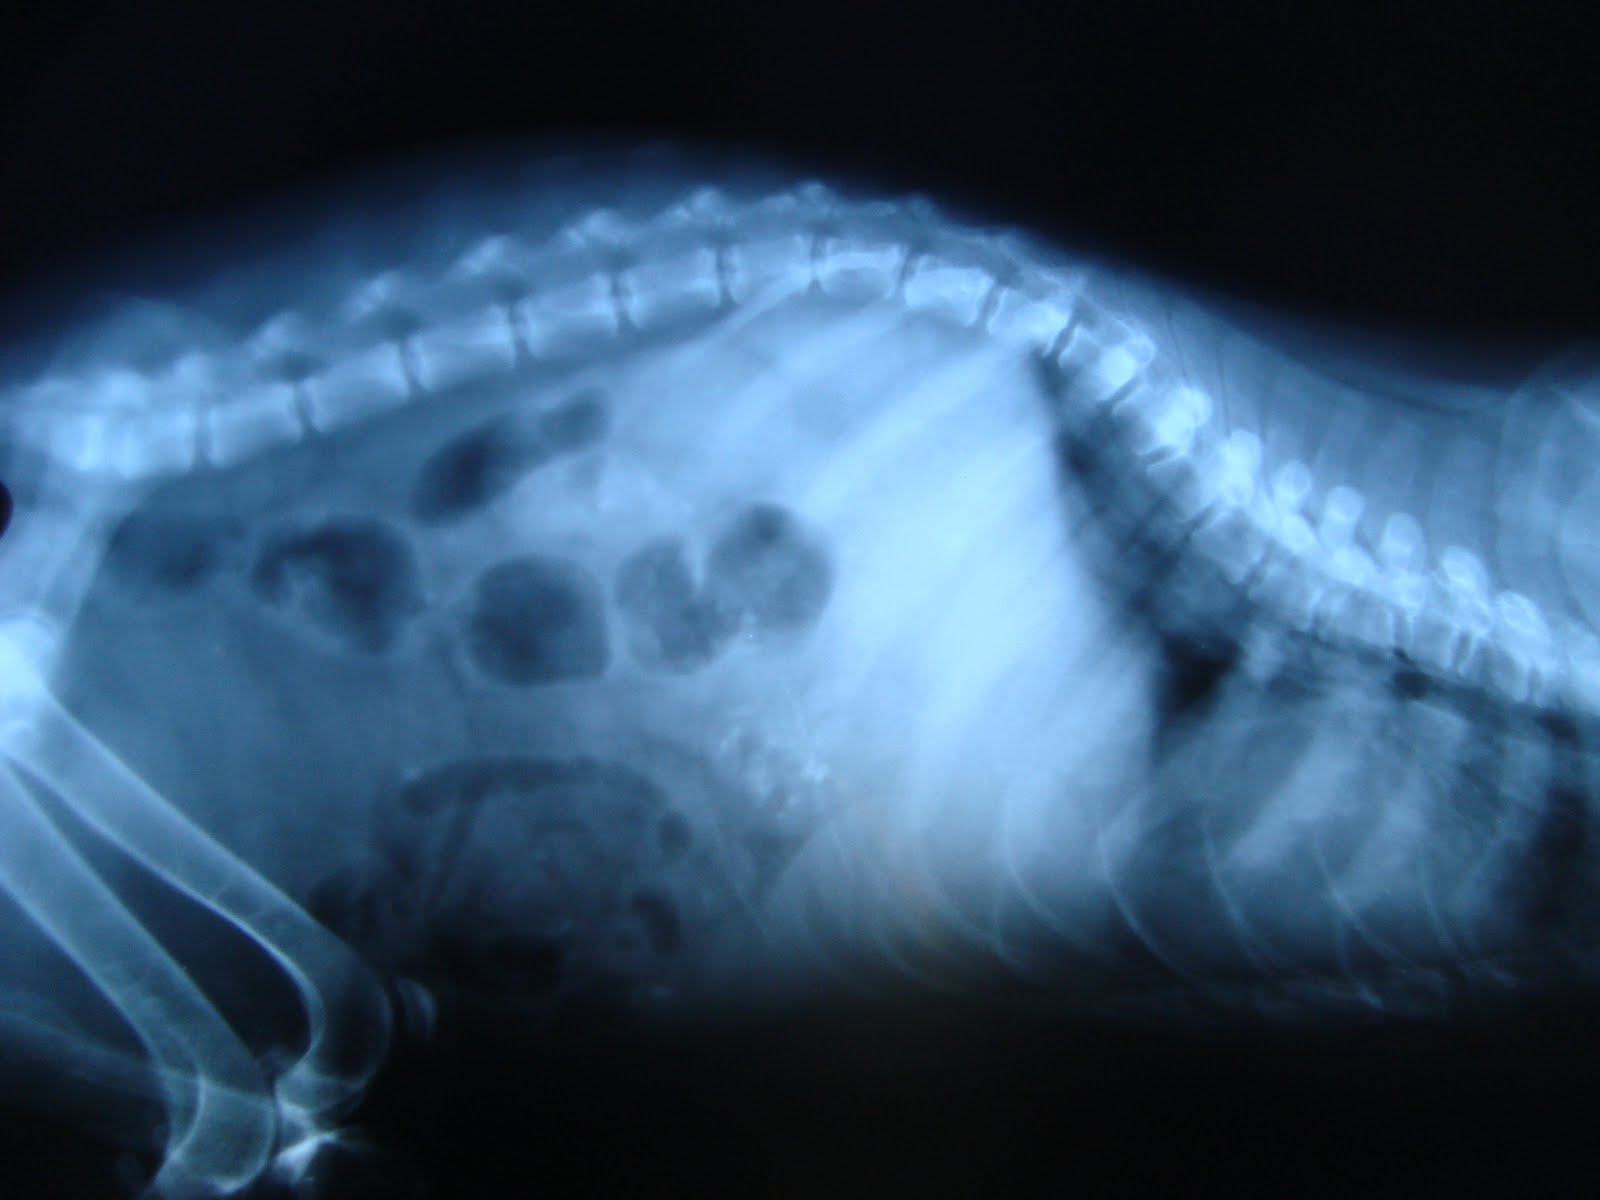

Dogs with Enlarged Hearts (Dilated Cardiomyopathy) Causes, Treatments

Final Video How to know whether a dog has an enlarged heart? Vertebral Is Exercise Good For Dog With Enlarged Heart Break your routine and find. Uncover the surprising benefits and risks of keeping your furry friend. We give our top tips on how to look after your dog at home if they have a heart condition, such as heart. discover the truth: Delicate activity can assist with further developing. While exercise is an essential component of a healthy lifestyle,. Is Exercise Good For Dog With Enlarged Heart.